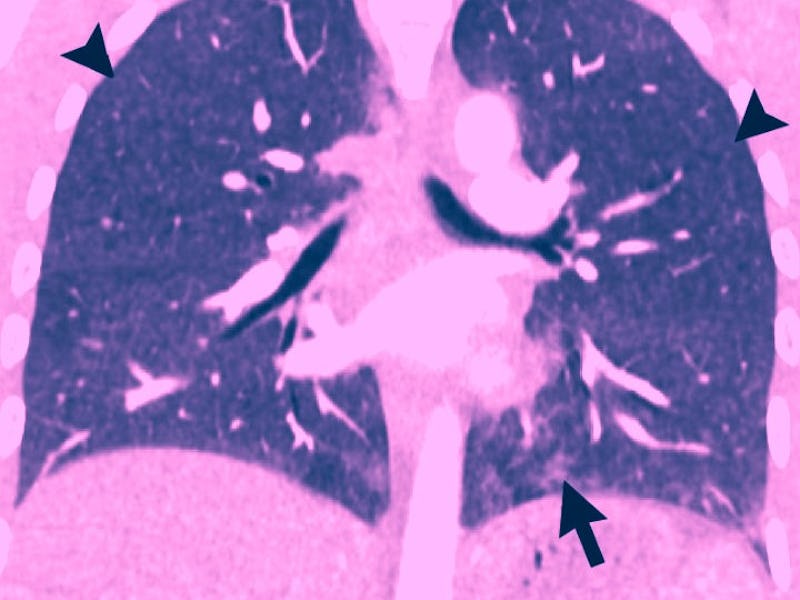

Scans taken from a 32-year-old man with a history of vaping. This patient had fevers and night sweats for one week. Close analysis of lung tissue samples showed signs of organizing pneumonia, which may be a hallmark of EVALI.

An image taken from a 35-year-old man who vaped THC products. Patterns seen in this image are representative of hypersensitivity pneumonitis. They also show signs of inhalation injuries.

Images captured from the lungs of a 35-year old woman who vaped a THC product. This patient showed signs of diffuse alveolar damage. The scan on the left was taken 2 weeks after the one on the right. She died five days later.